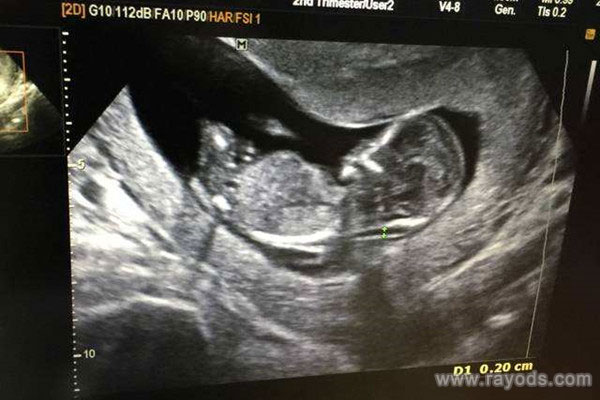

nt临界值是2.5还是3 nt值临界宝宝正常吗

产检,不仅可以看到胎儿的发育情况,对于孕妇来说也是一种身体监测。怀孕之后,随着孕周的增加,相应的产检项目和作用也会有所不同。一般来说,怀孕到了11-13周的时候孕妇..